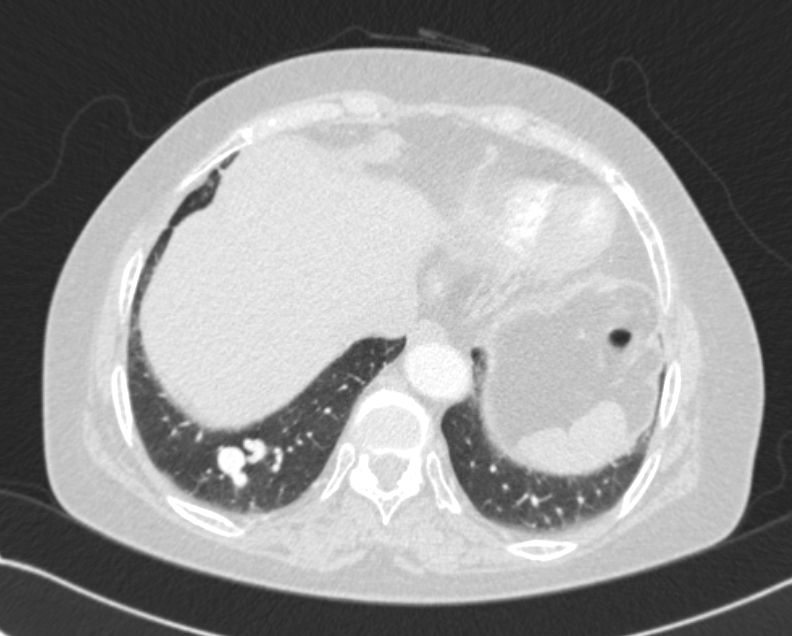

63¼¼ ¿©È¯

°©»ó¼±¾ÏÀ¸·Î ¼ö¼ú ¿¹Á¤À¸·Î, ¼ö¼ú Àü evaluation »ó¿¡¼­ CXR abnormality ÀÖ¾î

chest CT ±îÁö ½ÃÇàÇÏ¿´½À´Ï´Ù.